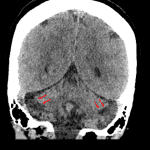

Age: 37

Sex: Female

Indication: Headache